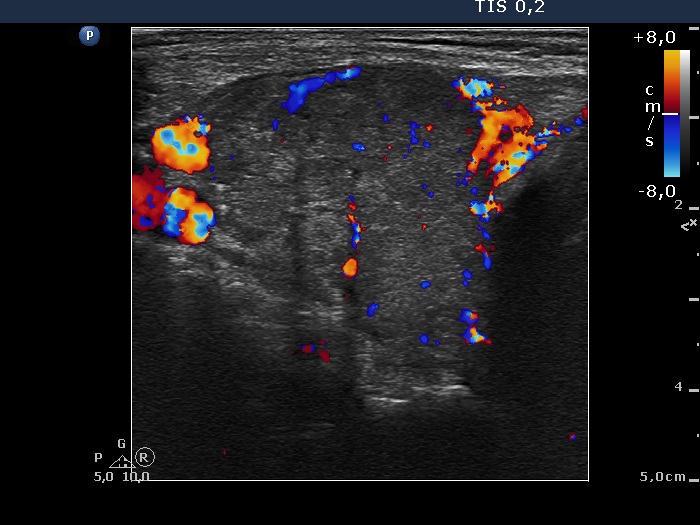

Right lobe, longitudinal scan

Right lobe, transverse scan, color Doppler mode. The vascularization is increased.